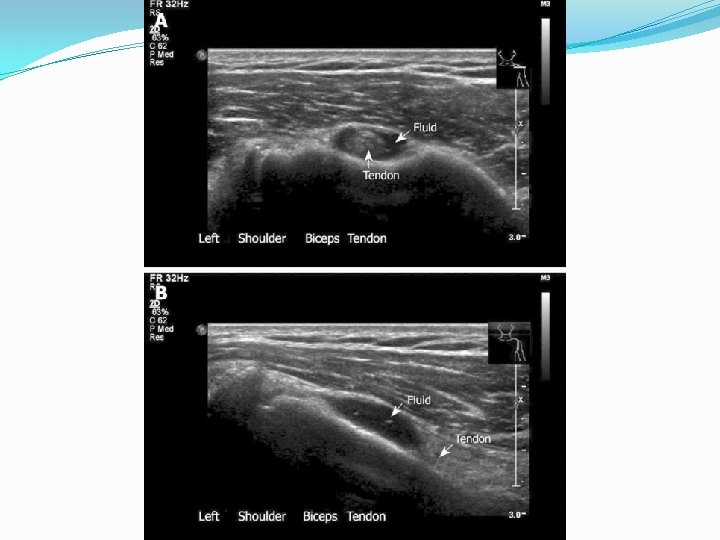

Sonography of Patients with Hemiplegic shoulder pain after stroke Lee et al Am J Roentgen 2009 Feb; 192(2): �n=71, 20 pts had bilateral shoulders scanned �Subacromial bursal effusion seen in 36 shoulders �Biceps tendon sheath effusion in 39 shoulders �Supraspinatus tendinosis (7), partial tear (6) and full tear (2) �Abnormalities more common in hemiplegic shoulder p=. 007 vs uninvolved side

Sonography and physical findings in stroke patients with hemiplegic shoulders: A longitudinal study Ya Ping Pong et al, J of Rehab med 2012, (44), 553 -557 � 76 first time CVA, no hx of shoulder problems �Scanned during acute rehab and at 6 mo �Underwent standard inpt rehab program 1 hour PT and 1 hr OT 5 d/wk �Brunnstrom score, ROM, Ashworth, 10 pt NRS

Sonography and physical findings in stroke patients with hemiplegic shoulders: A longitudinal study Ya Ping Pong et al, J of Rehab med 2012, (44), 553 -557 Acute (D/C from Rehab) Chronic (6 mo post D/C) �Subacromial effusion 30. 3% �Supraspinatus tear 30. 3% �Biceps tendon 39. 5% �Subscapularis 9. 2% �Pain score 2. 71/10 �Subacromial effusion 13. 2% �Supraspinatus tear 40. 8% �Biceps tendon 57. 9% �Subscapularis 22. 4% �Pain score 3. 99/10